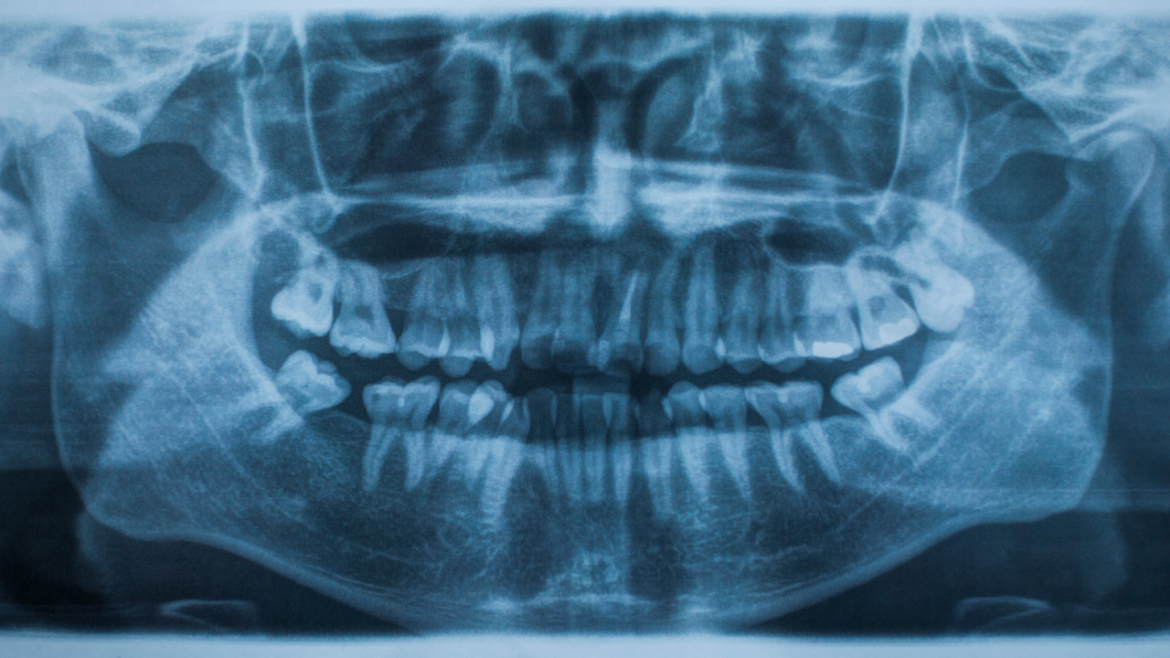

In particular, as to the sort of radiation, the mechanism focuses on the generation of X-ray, a type of electromagnetic radiation that ranges between ultraviolet light and gamma rays. Radiant energy in the X-ray range is greater than ultraviolet but less than gamma rays; X-rays can be used in several ways, for example, in medical diagnosis and non-destructive testing.

The chance for X-raying materials and the ionizing characteristics of X-rays have made them useful in different areas, especially in health facilities, industries and security.

While using X-rays has its advantages, it is also fraught with certain risks and hazards resulting from ionising the X-rays’ ionising ability. Ionization is unfavourable for biological tissues because it may cause symptoms such as DNA radiation and cancer. However, it has to be mentioned that those levels in dental imaging tend to be low, and, most of the time, the benefits of X-ray exams will overshadow the risks by light years.